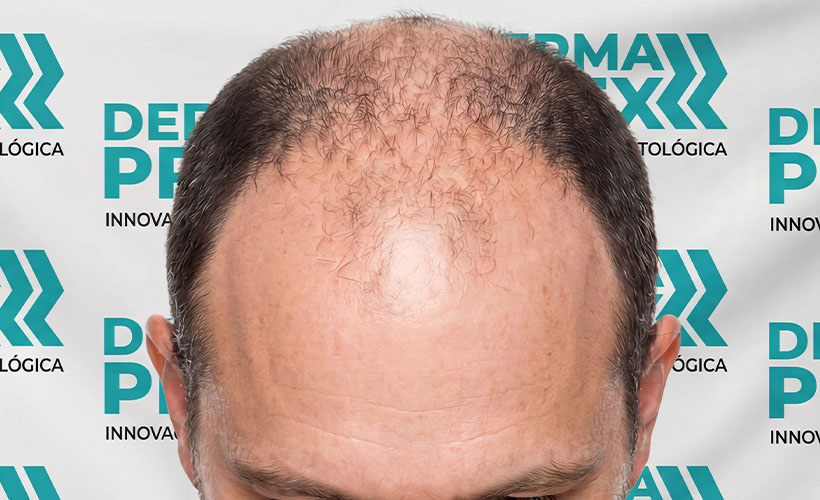

Resultados reales, confianza real

Cada tratamiento capilar cuenta una historia… y estas son las que más nos inspiran.

En esta sección encontrarás casos reales de personas que decidieron dejar de improvisar y empezar un tratamiento adecuado para su tipo de caída, logrando mejoras visibles en el crecimiento, fortalecimiento y salud de su cabello.